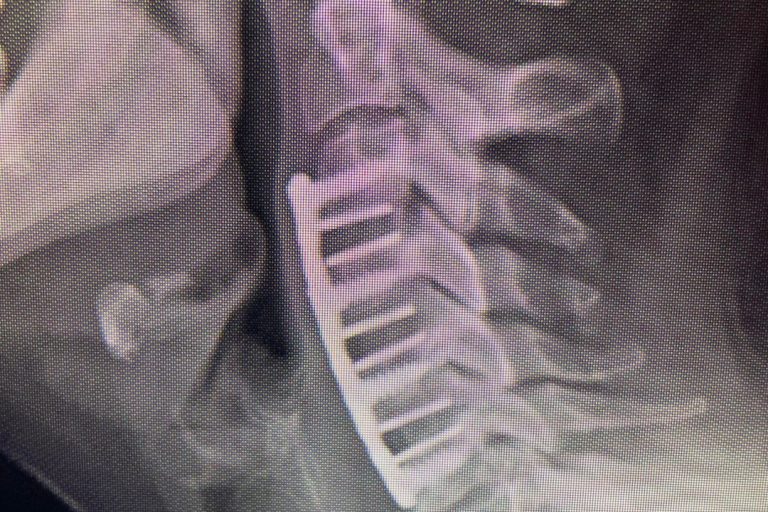

Cervical total disc replacement or disc arthroplasty is becoming an increasingly popular procedure. Now, the cervical disc replacements are even approved for doing 2 levels, as in this recent case that I performed. Is it right for you? Many things are possible in spine surgery but only a few things are most appropriate for you…